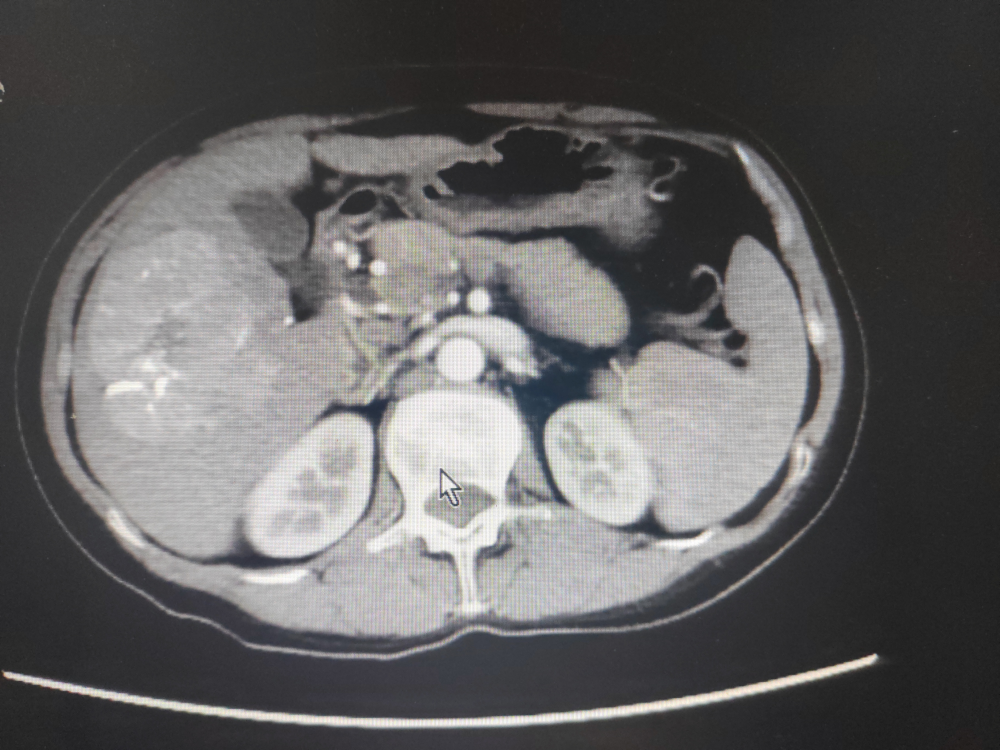

2022年3月7日上腹部增強CT